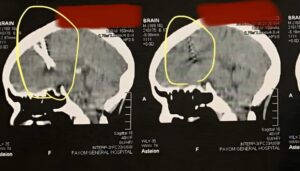

وكان المفاجأة الكبرى، أن الأشعة أظهرت وجود مسمارين معدنيين داخل الجمجمة، دون أن تكون المريضة على علم بهما، ودون أي أعراض ظاهرة على سطح الرأس أو أي مكان بروز تحت الجلد.

المريضه لم تتذكر الإصابة، لكن بعد نقاش معمق معها، تذكرت حادثة تعرضت لها منذ فترة قصيرة أثناء قيادة التروسيكل، حيث شعرت حينها بألم طفيف في رأسها ولم تعره اهتمامًا، ولم تكن تتخيل أن حادثًا بسيطًا قد يؤدي إلى اختراق مسمارين للجمجمة بطريقة دقيقة جدًا، بين نصفي المخ دون التسبب في أعراض واضحة.

أوضح الدكتور مصطفى عبد الحفيظ، أحد استشاريي المستشفى، أن هذه الحالة تعتبر استثنائية للغاية، حيث عادةً ما يسبب دخول أجسام معدنية صدمة أو نزيف أو أعراض عصبية واضحة، بينما هذه المريضة لم تظهر عليها أي علامات إصابة خطيرة على الإطلاق.

وتشير التحليلات الطبية إلى أن الجسم الغريب، في هذه الحالة المتمثل في المسمارين، لم يتسبب في أي تلف للمخ أو الأعصاب المحيطة، ما جعل المريضة تبدو طبيعية تمامًا عند الفحص السريري الأولي.